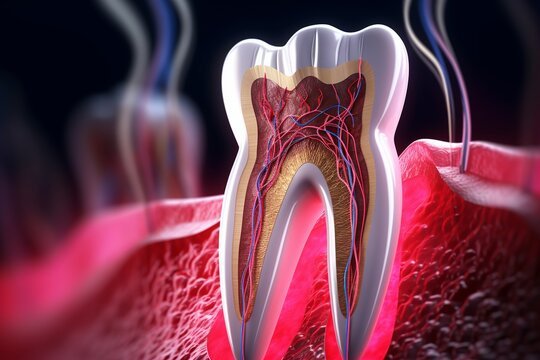

Root canal treatment is a vital dental procedure aimed at saving teeth that are severely damaged or infected. At Devdhar Dent Care in Greater Noida, we offer cutting-edge root canal treatments to alleviate pain, eliminate infection, and restore your tooth’s functionality. Our expert team uses advanced techniques to ensure a comfortable experience while preserving your natural tooth. Trust us for effective solutions that promote long-term oral health and a confident smile.

At Devdhar Dent Care in Greater Noida, our expert team ensures a comfortable and effective root canal treatment experience. Say goodbye to tooth pain and hello to a healthy, confident smile!